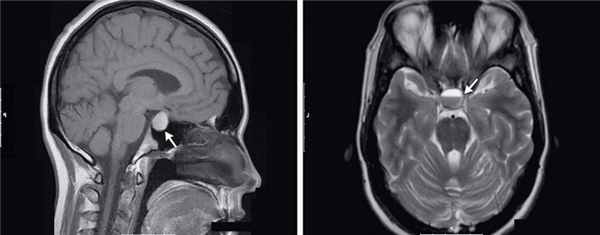

Гипофиз — железа внутренней секреции, расположенная в турецком седле основной кости черепа. Гипофиз состоит из передней и задней доли. Передняя доля — аденогипофиз, задняя доля — нейрогипофиз. Нарушения работы гипофиза проявляется в виде усиления выработки гормонов (например, как при аденомах гипофиза) и недостаточности выработки гормонов. Это в свою очередь приводит к нарушению эндокринно-обменных процессов и внутреннему дисбалансу.

Гипофиз — это эндокринная железа, массой около 0,5 г, располагается в гипофизарной ямке турецкого седла клиновидной кости и отделен от полости черепа отростком твердой оболочки головного мозга, образующим диафрагму седла.

В гипофизе различают две доли — переднюю (аденогипофиз) и заднюю (нейрогипофиз). Гипофиз и гипоталамус вместе с их нейроэндокринными, сосудистыми и нервными связями принято рассматривать как гипоталамо-гипофизарную систему.